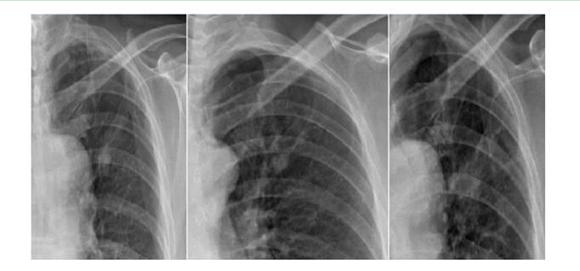

案例一:

第一年 第二年 第三年

案例解析:

在該案例中,病患在單一胸片檢查中,診斷出左上肺高密度結節影,前兩次在胸片攝影檢查得出的診斷結果并無大礙。相隔一年再去復查被誤診為“結核硬結灶”,并針對此而治療。但是,到了第三年之后,再次診斷發現結節影明顯增大,后才被確診為是肺癌,但為時已晚;如使用具備可視化點片功能的DR設備,胸片與胸透無縫結合,在透視下對“高密度結節影”全方位、多角度的高清點片獲取更多的確診信息,進一步病理分析,第一時間得出確診結果,做到早發現、早治療,結果將會截然不同。